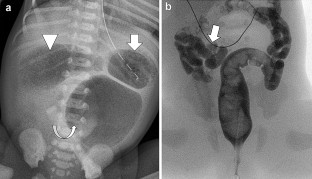

Nepal, P., Dukleska, K., Weiss, R.G. et al. Triple bubble sign of jejunal atresia. Abdom Radiol 46, 3512–3514 (2021). https://doi.org/10.1007/s00261-021-02974-4